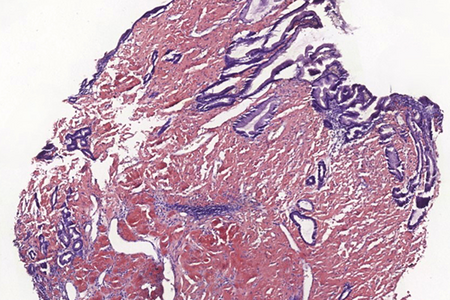

Histologically, lamina propria of gastric mucosa was expanded with amorphous paucicellular stromal deposits with cracking artifacts (Panels A and B). These depositions stained red with Congo Red stain (Panel C) and demonstrated characteristic apple-green birefringence in polarized light (Panel D). No malignancy was observed. Consequently, the final diagnosis was gastric amyloidosis.

Due to recurrent gastrointestinal bleeding and significant involvement of the stomach with amyloidosis, a distal resection of stomach was performed. Histological findings (Panel E) in the resection specimen, including Congo Red stain (Panel F) were similar to those described in the pre-operative biopsy.